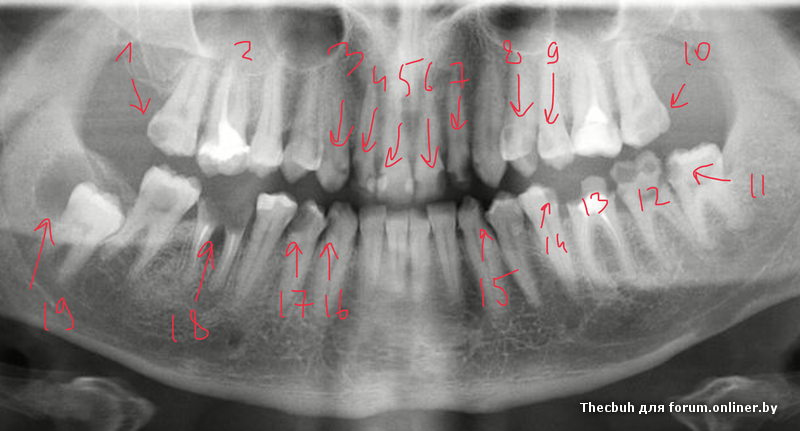

Здравствуйте, уважаемые врачи. Подскажите пожалуйста какие работы предстоит сделать.

Кратенько обозначим проблемы. Еще 26 реэндо

Thecbuh:Кратенько обозначим проблемы. Еще 26 реэндо

Эмм...Я вроде спросил что делать, а не какие у меня проблемы.

Лечить, удалять, протезировать.

Много лечить, удалять и тд . Вместо удаленных что захотите? Мосты или импланты? На передние пломбы с коронками или виниры(композитные/керамические)?

План лечения зависит еще и от ваших запросов

Примерно, такие-то удалять, протезировать, такие-то лечить, ставить коронки, такие-то лечить.

Понятно что, для детального плана нужен личный осмотр, знание запросов и возможностей, но примерные действия по каждому зубу вы же можете сказать.

Запросы простые: импланты, вставки коронки и "шоб смотрелось" (т.е. эстетика).

Во вторых. Предварительный план в данной ситуации можно составить только после очного осмотр. Окончательный же план протезирования будет после терапевтической подготовки.

В третьих по данному снимку можно составить 20 планов, а то и более планов лечения в зависимости от материальной обеспеченности.

nhtnbq, предварительно как-то так

Л-лечить

К- коронка

У- удалять